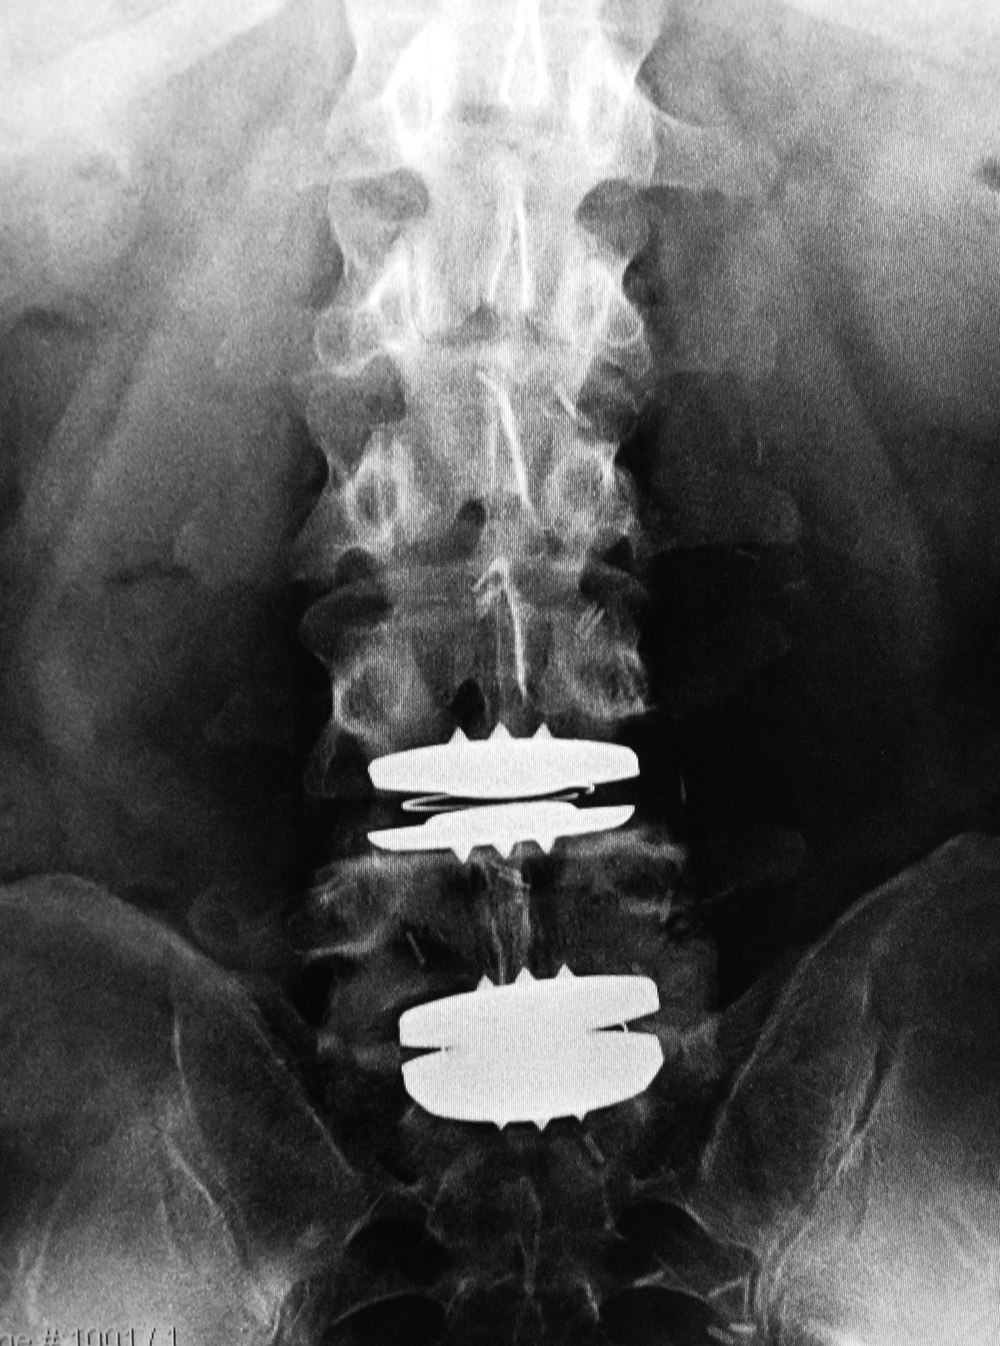

Metal-on-polyethylene total disk replacement at L4-5 and L5-S1 |

47 year-old man |

| Lumbar spine fusion and metal-on-polyethylene disk replacement at L4-5 and L5-S1 |

| 31 year-old man with chronic low back pain. In addition to the total disk replacements at L4-5 and L5-S1 there is also a laminectomy from L4 to S1 with posterolateral bony fusion masses and pedicle screws with connecting rods on each side. |